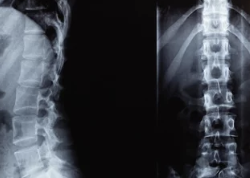

✅ 5. 척추측만증과 척추후만증 (척추 변형)

척추가 옆으로 휘는 척추측만증이나

척추가 앞뒤로 심하게 굽는 척추후만증도 허리 통증을 유발해요.

- 척추가 바르지 않으면 한쪽으로 허리 통증과 피로감 증가

- 오래 서 있거나 앉아있기 힘들고 만성 피로 유발

- 성장기에 주로 발생하지만, 성인도 악화될 수 있음

✔ 조기에 발견하여 자세교정과 근력 운동으로 관리해야 합니다.